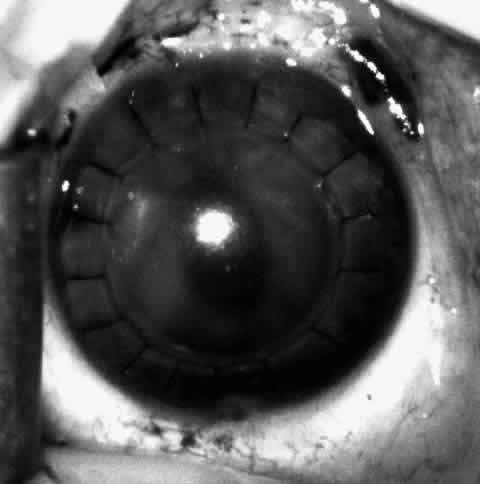

Sixteen to 22 interrupted 10-0 nylon sutures are placed to secure the edge of the lens in the peripheral corneal stroma trough. The first eight sutures are placed with the edge of the lens lying over the circular trephine mark (Fig. 10). As with any corneal transplant surgery, the second suture is the most important in centering the lens. All knots must be tied in such a way that the knots may be buried easily. At the same time, the sutures must not be tightened so tightly that compression occurs with the lens. My personal preference is for a 2-1-1 surgeon's knot. Care should be taken to prevent the lens from being sewn eccentrically into the bed, to prevent astigmatism. After the first eight sutures are placed, the edge of the lens is tucked into the stromal bed all around (Fig. 11) and the remaining 8 to 14 sutures are placed to fasten the lens securely in place (Fig. 12). The sutures are rotated so that the knots are buried in the recipient cornea. This allows the surgeon to remove the sutures at a subsequent examination under anesthesia (EUA) by means of traction directed peripherally without dehiscence of the wound.

Fig. 12. The remaining eight sutures are placed with the lenticule edges tucked.